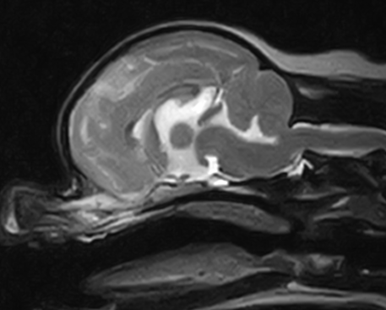

犬種 チワワ

年齢 7歳齢

体重 2.95kg

性別 去勢雄

運動失調(ふらつき、登れていた段差も登らなくなった)の主訴で来院。

初診から4か月後に重積発作で来院されたため、MRI検査を実施。

MRI検査:

右前頭葉にT2 強調画像/FLAIR 画像で高信号、T1 強調画像で一部低信号を示し、辺縁部で一部造影増強を示すびまん性の所見を認めた。この所見は、DWI 画像で高信号、ADC-map で大半が等~低信号を示していた。また左側前頭葉にも同様の信号所見を示す微小病変を認めた。

T2強調画像 矢状断像